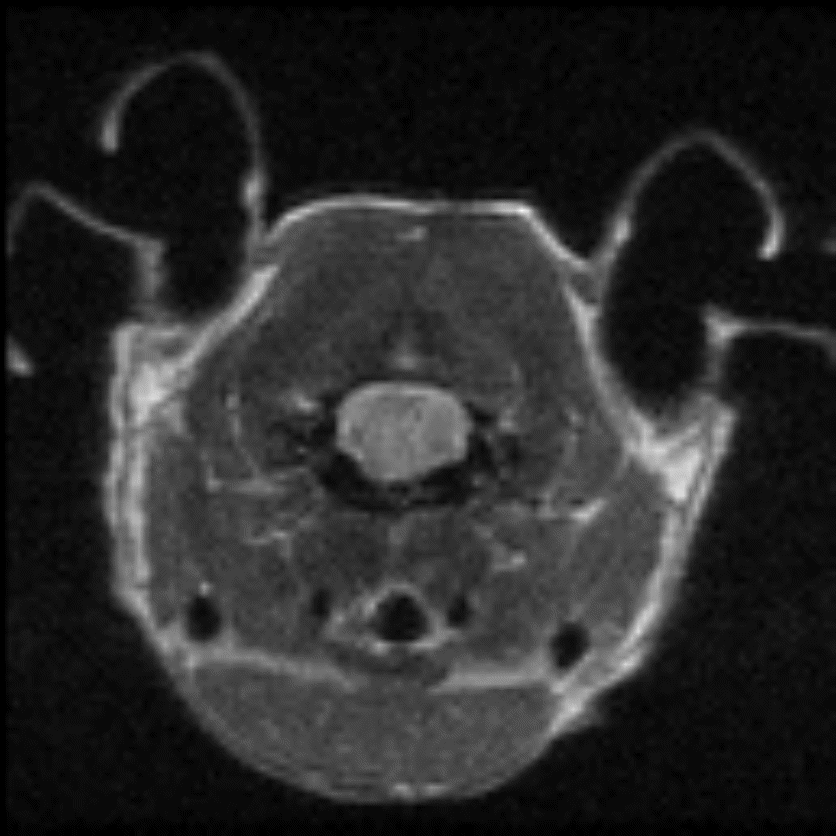

Cardiac Cine loop images: Long axis view of a single slice of the heart was acquired with Cine loop images. Long-axis images can be used for strain analysis in third-party software. Image Credit: Scintica Instrumentation Inc

Short axis view of a single slice of the heart was acquired with Cine loop images. Short axis images can be used to analyze functional measurements in third-party software. Image Credit: Scintica Instrumentation Inc